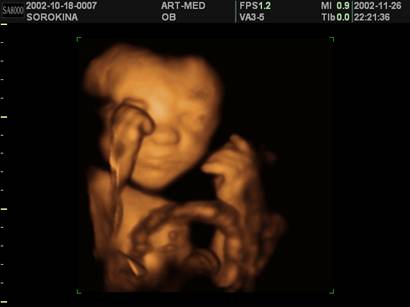

УЗ-сканирование плода (УЗ-диагностика) - исследование состояния плода с помощью ультразвукового аппарата является одним из основных методов ПД (рис. 7.4.5, 7.4.6). УЗ исследование позволяет выявить 80 - 98 % плодов с анатомическими пороками и в настоящее время широко используется в нашей стране для скрининга патологии беременности. Метод особенно информативен на сроке 18 - 20 недель беременности.

Рис. 7.4.5. Изображение 4D УЗ-исследования